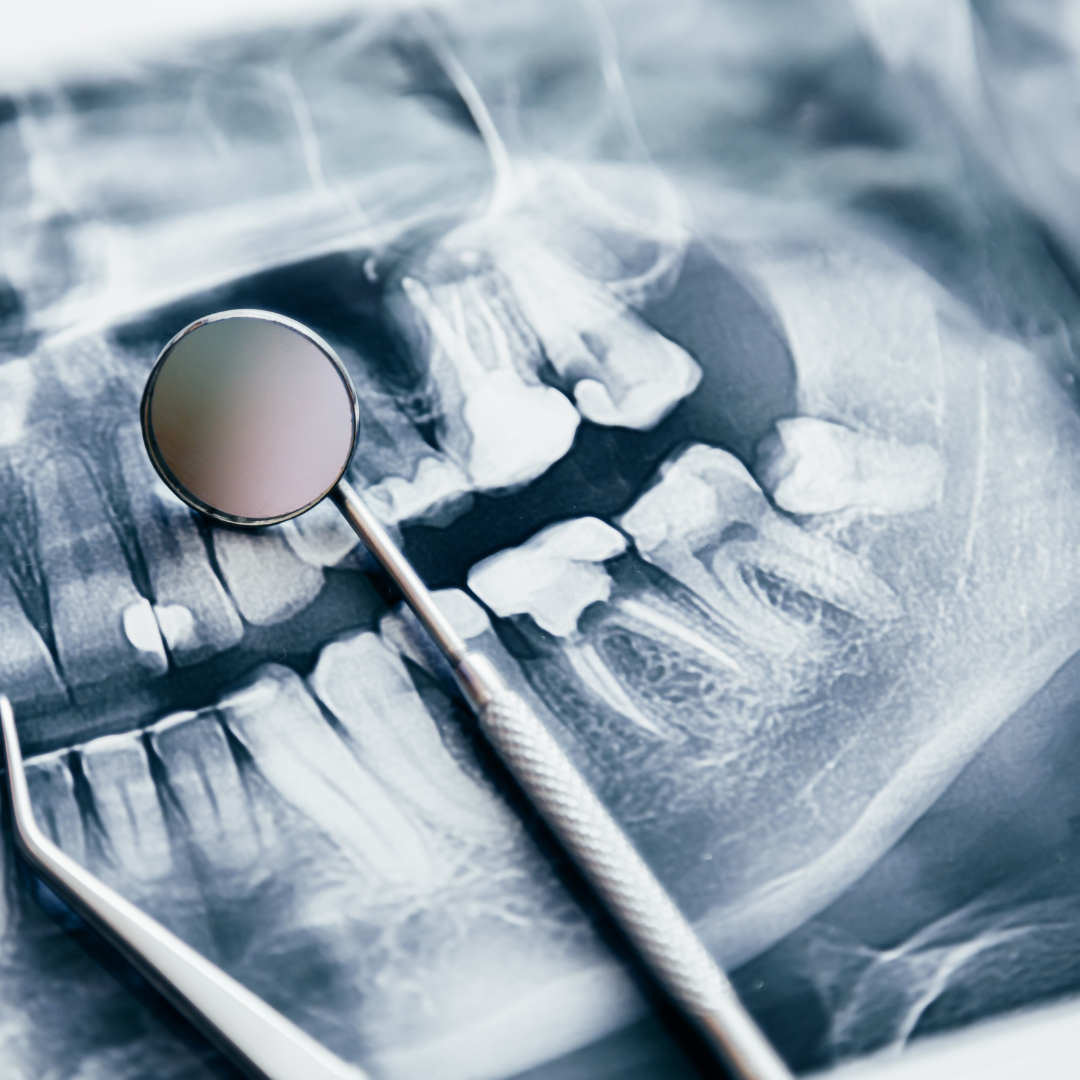

ডিজিটাল এক্স-রে হল এমন একটি ইমেজিং প্রযুক্তি যেখানে রেডিওগ্রাফিক ডিটেক্টরের মাধ্যমে এক্স-রে রশ্মি ধরে কম্পিউটারে উচ্চ-মানের ছবি তৈরি করা হয়। এটি ঐতিহ্যবাহী ফিল্ম-ভিত্তিক এক্স-রের তুলনায় দ্রুত এবং কার্যকর।

ডিজিটাল এক্স-রে প্রধানত দুই ধরনের হয়ে থাকে:

ডিজিটাল এক্স-রে চিকিৎসা ও দন্তচিকিৎসার বিভিন্ন ক্ষেত্রে ব্যাপকভাবে ব্যবহৃত হয়। নিচে এর কিছু ব্যবহার উল্লেখ করা হলো:

ডিজিটাল এক্স-রের মাধ্যমে নানান সুবিধা পাওয়া যায়, যেমন:

ডিজিটাল এক্স-রে ব্যবহারের কিছু সীমাবদ্ধতাও রয়েছে, যেমন:

ডিজিটাল এক্স-রে এবং প্রচলিত এক্স-রের মধ্যে কিছু উল্লেখযোগ্য পার্থক্য রয়েছে:

ডিজিটাল এক্স-রে আধুনিক চিকিৎসা ক্ষেত্রে বিপ্লব এনেছে। এটি রোগ নির্ণয়ে আরও নির্ভুলতা, নিরাপত্তা এবং গতি নিশ্চিত করেছে। উন্নতমানের ইমেজিং এবং কম রেডিয়েশন একে ভবিষ্যতের চিকিৎসা প্রযুক্তির অন্যতম সেরা উদ্ভাবন করেছে। তাই, চিকিৎসা ক্ষেত্রে উন্নত মানের রোগ নির্ণয়ের জন্য ডিজিটাল এক্স-রে বেছে নেওয়াই সেরা সিদ্ধান্ত।

X-rays are essential in dentistry to detect problems not visible to the naked eye. Digital X-rays, an advancement over traditional methods, use less radiation and provide immediate.